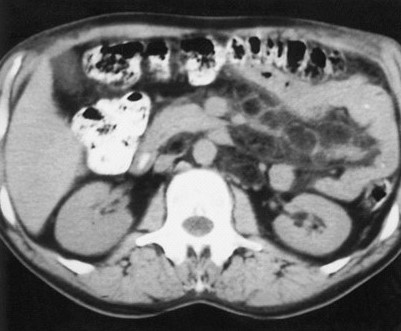

Panel B

The CT scan of the abdomen shows attenuation of the mesentary in a pattern of rounded, well-circumscribed nodules, 1 to 2 cm in diameter, with soft-tissue rims and fatty centers (left image). The barium enema examination shows slightly thickened folds and separated loops in the proximal small bowel (right image).